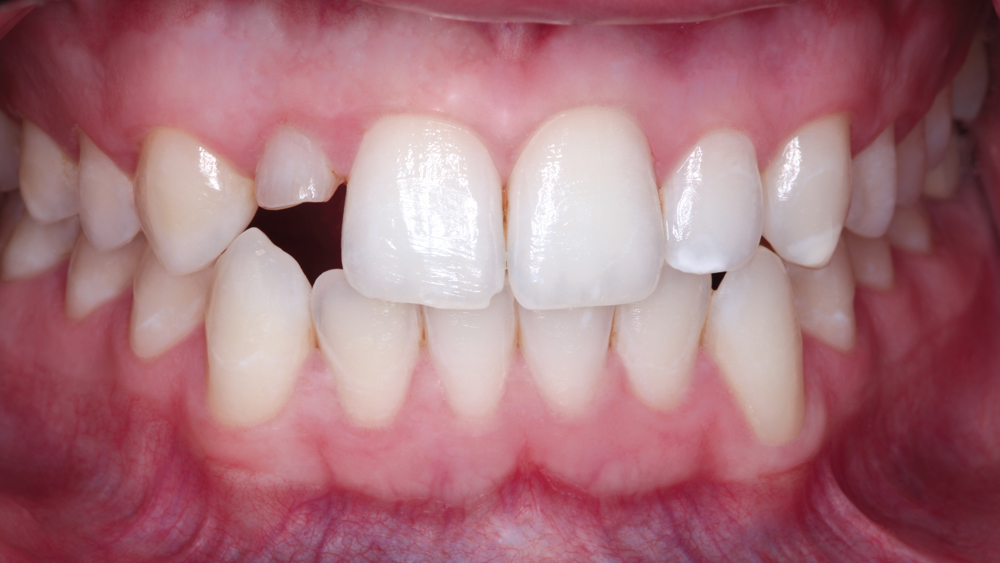

The following case illustrates the efficient, straightforward clinical workflow for placing Hahn Tapered Implants via guided surgery. A digital treatment plan is developed in which a 3.5 mm implant is positioned to support the ideal prosthetic outcome. An immediate provisional crown is designed in concert with the surgical guide and delivered at the time of surgery, helping to produce a predictable, highly esthetic restoration for a demanding case in the smile zone.